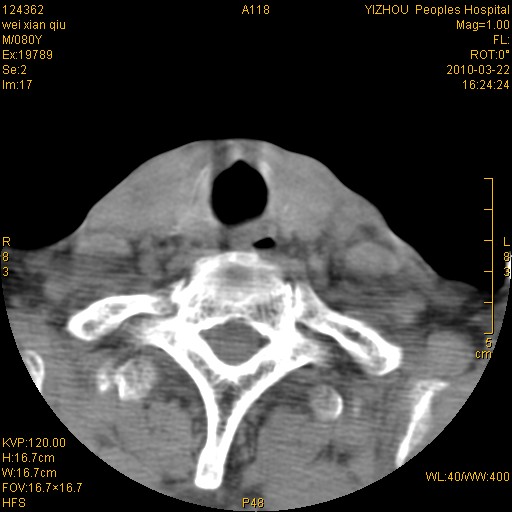

标题: CT25263:喉部占位?

男,80岁.声嘶三月余.

右侧喉癌可能性大,建议喉镜检查

喉前庭右侧壁明显增厚,并见向内突出的软组织密度新生物,表面光滑,其后方软组织层次尚清晰,多考虑:喉部乳头状瘤!建议喉镜并病检!

右侧声们下区新生物